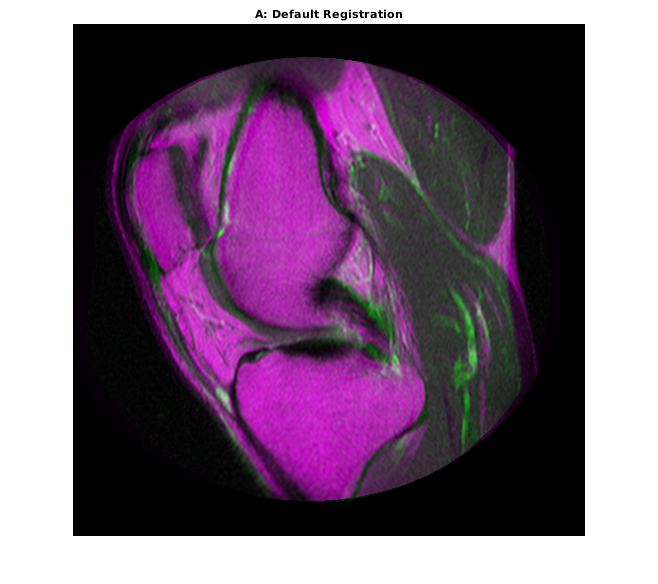

Очень, очень редко, что imregister выровняет изображения отлично с настройками по умолчанию. Тем не менее, использование их является полезным способом решить который свойства настроиться сначала.

movingRegisteredDefault = imregister(moving,fixed,'affine',optimizer,metric); imshowpair(movingRegisteredDefault,fixed) title('A: Default Registration')

Первичная регистрация не очень хороша. Существуют все еще значительные области плохого выравнивания, особенно вдоль правого края. Попытайтесь улучшить регистрацию путем корректировки оптимизатора и метрических свойств настройки.